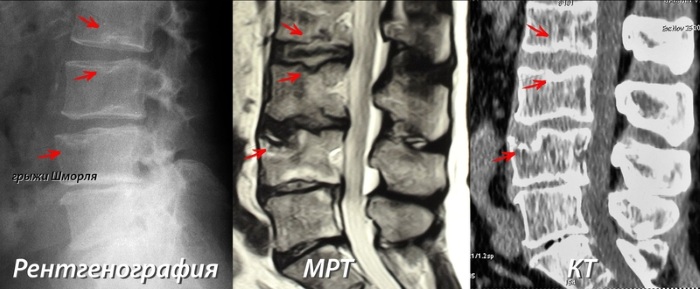

Грыжа Шморля на позвоночнике диагностируется довольно просто, но врачи всегда используют несколько методов для оценки общего состояния больного:

- Рентгенография позвоночного столба в разных проекциях считается наиболее эффективным методом диагностики. Поскольку помогает выявить степень поражения тканей и количество очагов в позвоночнике. После изучения снимков врач назначает дополнительное исследование и лечение.

- Магнитно-резонансная томография позвоночного столба используется в качестве дополнительного метода диагностики. Назначается в случае, когда при проведении рентгенографии не позволяет в точности определить степень поражения тканей.